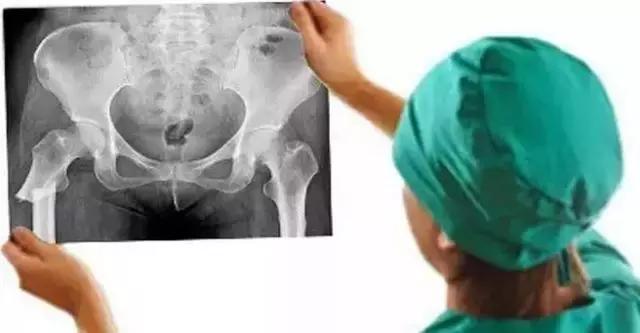

大查房见到一女性病人,57岁,洗澡时地滑导致股骨粗隆下骨折。粗隆下骨折多见于青壮年高能量外伤后,而眼前的病人是一位白净的中年女性,仅仅是洗澡过程中骨折,按说致伤能量不是很高,当时首先想到的是肿瘤骨转移的病理骨折,反复查看X线片和CT后不符合肿瘤骨转移病理骨折。王晓宁主诊医生再次补充病史:患者因内科疾病长期服用激素。服用激素能够导致骨坏死和骨质疏松,骨坏死常见于股骨头,骨质疏松骨折多见于股骨近端。带着疑问全科医生仔细阅读影像资料料,此例粗隆下骨折表现的仅是简单骨折(图1),而经典的粗隆下骨折多是粉碎或长螺旋形(图2、3)。全科医生畅所欲言,充分发表各自看法,却不能完美解释上述疑问,按现有医疗水平处理此类骨折不是难事,但解除不了内心的疑惑。经过激烈讨论后,决定暂缓手术、寻找证据、明确骨折原因。大家分头查找文献,两天后再次讨论。